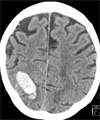

David Mendelow, Professor of Neurosurgery at Newcastle University and honorary consultant within the Newcastle Hospitals NHS Foundation Trust, who ran the trials, has devised a formula published today online in The Lancet which will allow surgeons to calculate when to intervene with surgery after an Intracerebral Haemorrhage. This occurs when the blood escapes from the blood vessels into the brain itself to produce a solid clot.

Image shows a scan of intracerebral hemorrhage.